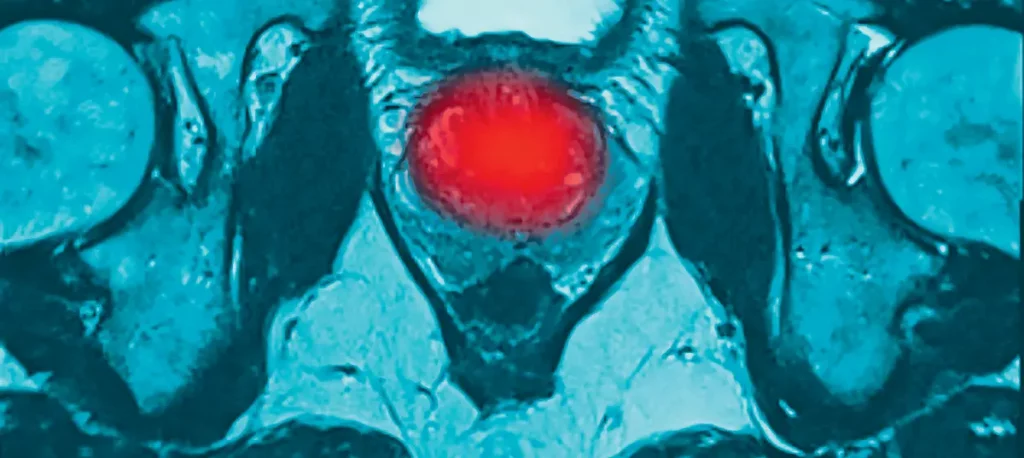

Bei der Früherkennung des Prostatakarzinoms (PCa) ist in letzter Zeit der Empfehlungsgrad für die multiparametrische Magnetresonanztomografie (mpMRT) gestärkt worden. Diese sollte bei erhöhtem PSA vor einer Prostatastanzbiopsie erfolgen. Bisher war jedoch unklar, wie sicher es ist, bei einem negativen MRT-Befund auf die Biopsie zu verzichten und regelmäßig ein nichtinvasives Monitoring vorzunehmen. Diese Frage wurde in einer großen Längsschnittstudie unter Federführung der Charité – Universitätsmedizin Berlin untersucht.

Es ist eine prospektive Längsschnittkohortenstudie in Kooperation von 54 urologischen Praxen mit 2 universitären radiologischen Zentren. Teilgenommen haben 593 erwachsene Männer bis 70 Jahre (median: 64 Jahre) mit Verdacht auf PCa wegen eines erhöhten PSA-Wertes, eines auffälligen Befundes der digito-rektalen Untersuchung oder von beidem. Es gab keinen vordefinierten PSA-cut-off, dieser wurde durch die Behandler bewertet. Bei Abklärungsbedarf erfolgte eine mpMRT-Untersuchung, die nach der PI-RADS-Klassifikation bewertet wurde (Score 1–5, Karzinom sehr unwahrscheinlich–sehr wahrscheinlich). Bei einem Wert von ≥ 3 wurde der MRT-Befund als positiv bewertet, darunter als negativ. In diesem Fall wurde empfohlen, auf die Prostatabiopsie zu verzichten und aktiv zu beobachten mit halbjährlichen Bestimmungen des Serum-PSA, einer digito-rektalen Untersuchung und Ultraschall. Endpunkt war der Anteil der Teilnehmer, bei dem unter aktivem Monitoring über 3 Jahre Biopsien vermieden konnten, sowie der Anteil mit PCa.

Bei fast der Hälfte der 593 Teilnehmer, die wegen des Verdachts auf Prostatakarzinom mit mpMRT untersucht wurden, war der Befund negativ (n = 286; 48,2 %). 242 Patienten (41 %) konnten über 3 Jahre eine Prostatabiopsie vermeiden. 307 Teilnehmer (51,8 %) hatten einen positiven mpMRT-Befund. Bei 161 (27 %) wurde in den sich direkt anschließenden Biopsien ein klinisch relevantes Karzinom entdeckt und bei insgesamt 29 % (n = 172) im 3-Jahres-Zeitraum. Das für 3 Jahre vorgesehene Monitoring nach negativem mpMRT beendeten 233 Männer. Bei 7 Patienten (3–4 %) wurde im Verlauf des Monitorings doch noch ein klinisch relevantes PCa festgestellt. Der negative Vorhersagewert eines mpMRT mit negativem Befund lag bei 96 %. Dr. rer. nat. Nicola Siegmund-Schultze

Fazit: Bei Verdacht auf Prostatakarzinom im Rahmen einer Früherkennungsuntersuchung lässt sich die Wahrscheinlichkeit für ein Karzinom zunächst mit einem multiparametrischen MRT (mpMRT) und ohne Stanzbiopsien abklären. Ist der mpMRT-Befund negativ, ist die Wahrscheinlichkeit sehr hoch, innerhalb von 3 Jahren nicht an einem aggressivem Prostatakrebs zu erkranken. Unter einem regelmäßigen und qualifizierten Monitoring kann vielen Männern dann die Prostatabiopsie erspart werden.